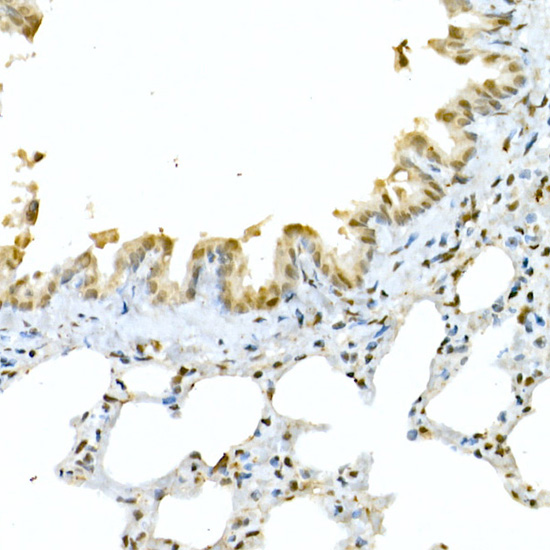

Immunohistochemistry analysis of paraffin-embedded Rat lung using CREB1 at dilution of 1:50 (40x lens).